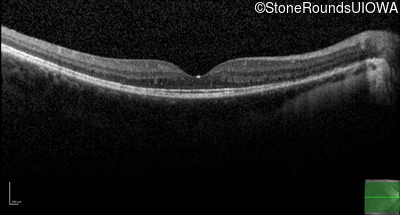

Optical Coherence Tomography - Right - 20/40 +1

Exemplar / OCT Stack

OCT Stack